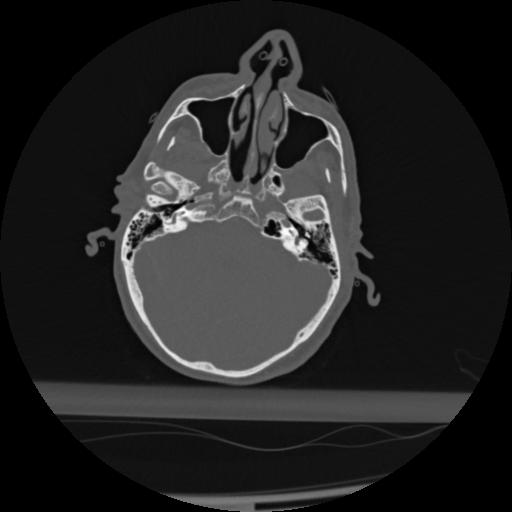

22 ANGIO,CE,Vol,0.5,ANGIO,,